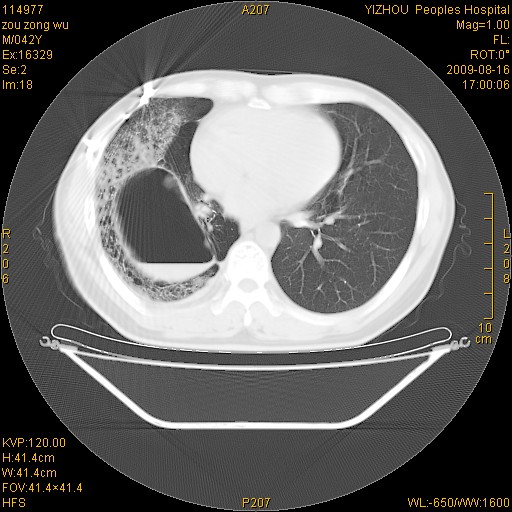

以下是引用zjzjr在2009-8-17 10:42:00的发言:[br]右侧间质性肺炎伴纤维化,右肺下叶肺囊肿伴感染(不除外外伤后引起),右肺野及胸壁软组织\\肝内见多发斑点状,中枪了吧.右侧胸膜肥厚\\粘连.